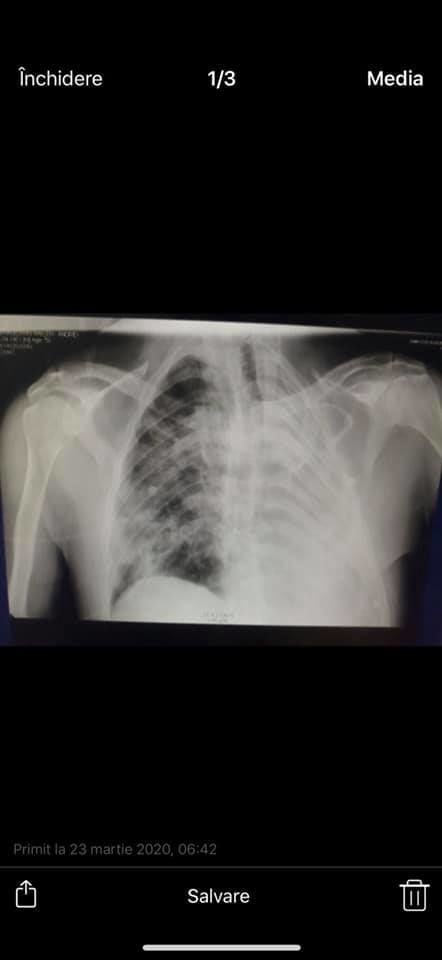

Știți ce-s cu pozele de mai jos? Raportul zilnic al medicilor reanimatologi-anesteziologi din terapia septică, unde stau internați pacienții gravi cu COVID-19. Zilnic, de la 06:00 dimineață, profesorul Anatol Ciubotaru primea radiografiile fiecărui asemenea pacient, le compara cu radiografiile din seara precedentă și discuta cu medicii tacticile de tratament în continuare, de ce au nevoie pacienții și medicii.

Pozele din viber din telefonul tatei, el nu știe că le postez și sper că nu încalc nimic, parcă nu-s date cu caracter personal după care să poată fi identificați pacienții. Pozele date au fost trimise de medicul de gardă dimineața când avea deja febră, dar era la datorie. El este un erou. Să avem grijă de eroii noștri... Profesorul Ciubotaru nu mai poate să o facă deja, iar premierul a promis că fără el se va îmbunătăți brusc situația epidemiologică în spital”, a explicat tânăra pe o rețea de socializare.